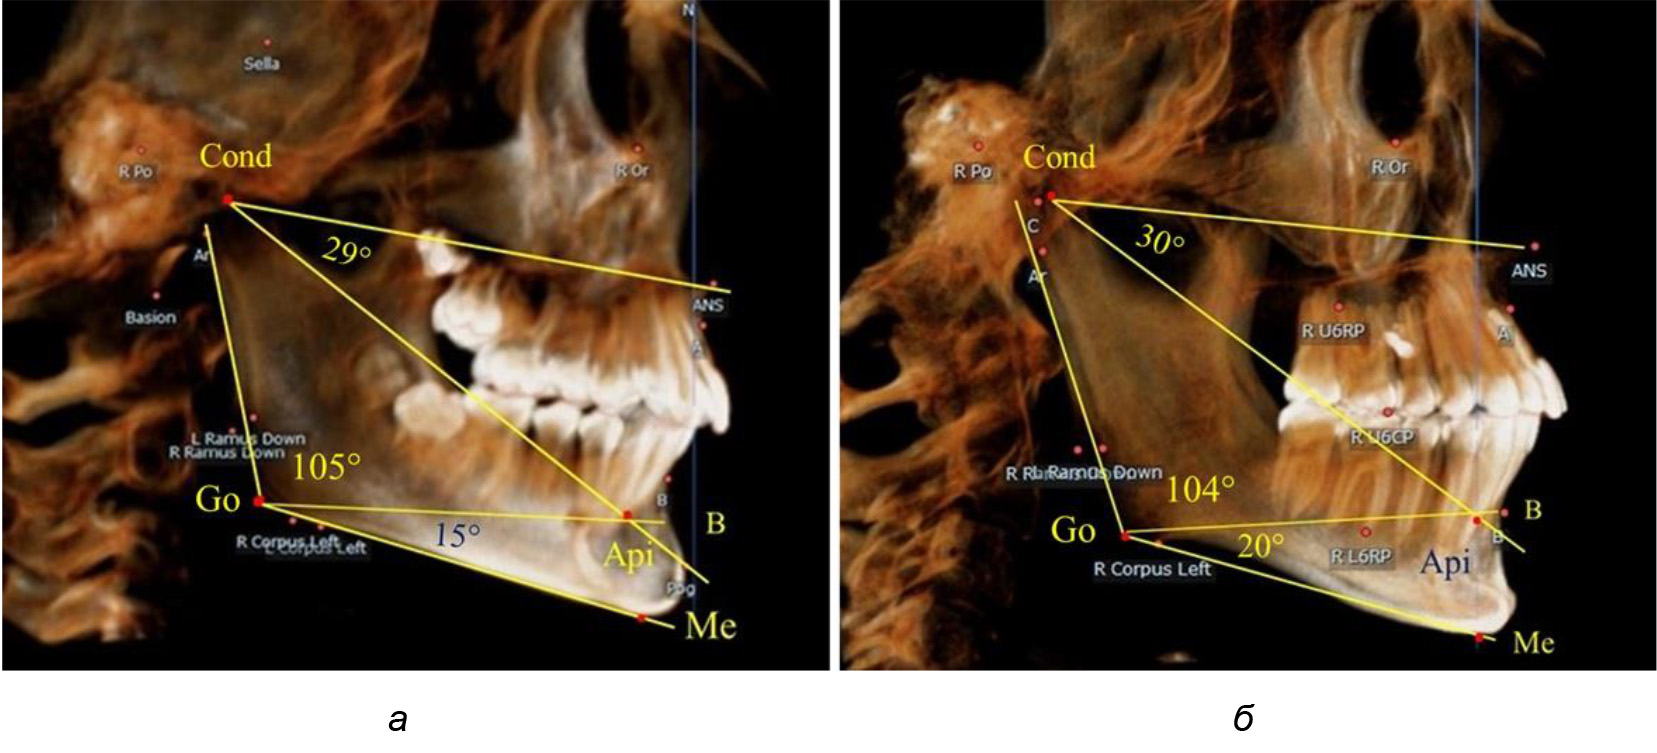

При анализе ТРГ 5 детей в периоде прикуса молочных зубов отмечено, что величина основного угла гнатической части лица SNA-Cond-Api, как правило, в норме составляла около 30°, и его величина была относительно стабильной у всех обследованных детей. В то же время угол нижней челюсти и его составляющие отличались вариабельностью параметров при различных показателях нижнечелюстного угла (рис. 4).

Рис. 4. Особенности ТРГ (а) и 3D-модели (б) в периоде прикуса молочных зубов

Таким образом, в периоде молочного прикуса с оптимальными окклюзионными соотношениями, несмотря на линейные размеры в вертикальном и сагиттальном направлении, которые, безусловно, меньше параметров взрослых людей, величина основного угла гнатической части лица SNA-Cond-Api соответствовала параметрам людей с полностью сформированным физиологическим прикусом постоянных зубов. Анализируя данные рентгенограмм детей в периоде сменного прикуса, отмечено, что величина основного угла гнатической части лица SNA-Cond-Api, так же как в молочном и постоянном прикусе, в норме составляла от 28 до 32°. В то же время угол нижней челюсти и его составляющие отличались вариабельностью параметров при различных показателях нижнечелюстного угла. Достоверных различий угла гнатической части после смены нижних медиальных резцов и прорезывания первых постоянных моляров (4 ребенка) не было; происходил очередной этап подъема высоты прикуса и увеличение линейных размеров костей гнатической части, однако угловые параметры были относительно стабильны. После смены всех резцов и замены первых молочных моляров первыми премолярами (6 человек) увеличивались линейные размеры при сохранившихся угловых показателях гнатической части лица (рис. 5).